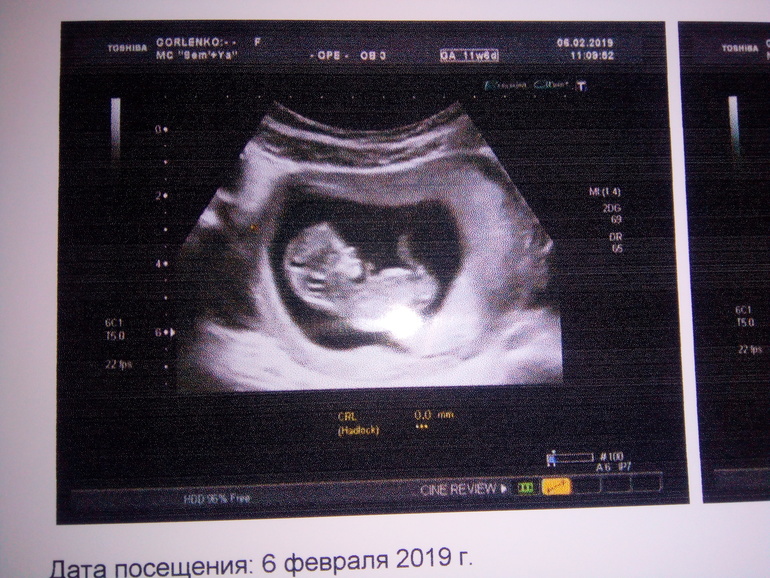

Первое УЗИ второго малыша. 11,6 недель.

Слава Богу, состояние потихоньку улучшается, и сегодня мы все втроём увидели нашего маленького 48-ми миллиметрового пупсика с громко стучащим сердечком в 155 ударов в минуту! Врач-УЗИст сказал, что всё в норме. Хотя, сразу, глядя на мой впавший живот с торчащими маслаками, думал, что через брюшную стенку ничего не будет видно, и заметно удивился, что уже 11,6 недель по акушерскому сроку. По УЗИ срок беременности ставят ровно 12 недель, а по КТР - 11,3 недели. Предположил, что мальчик, но это пока совсем не точно. Манюня прикрепился к задней стенке. Вопрос: из-за этого первые шевеления должны позже почувствоваться и живот меньше быть? Я с доченькой упустила из виду этот момент. Она затолкалась ровно в 18 недель в четверг (через 22 недели в четверг мы с ней встретились).

Сделали нам две распечатки с описанием и фото (одно на фотобумаге для нас, а второе на обычной - для поликлиники).